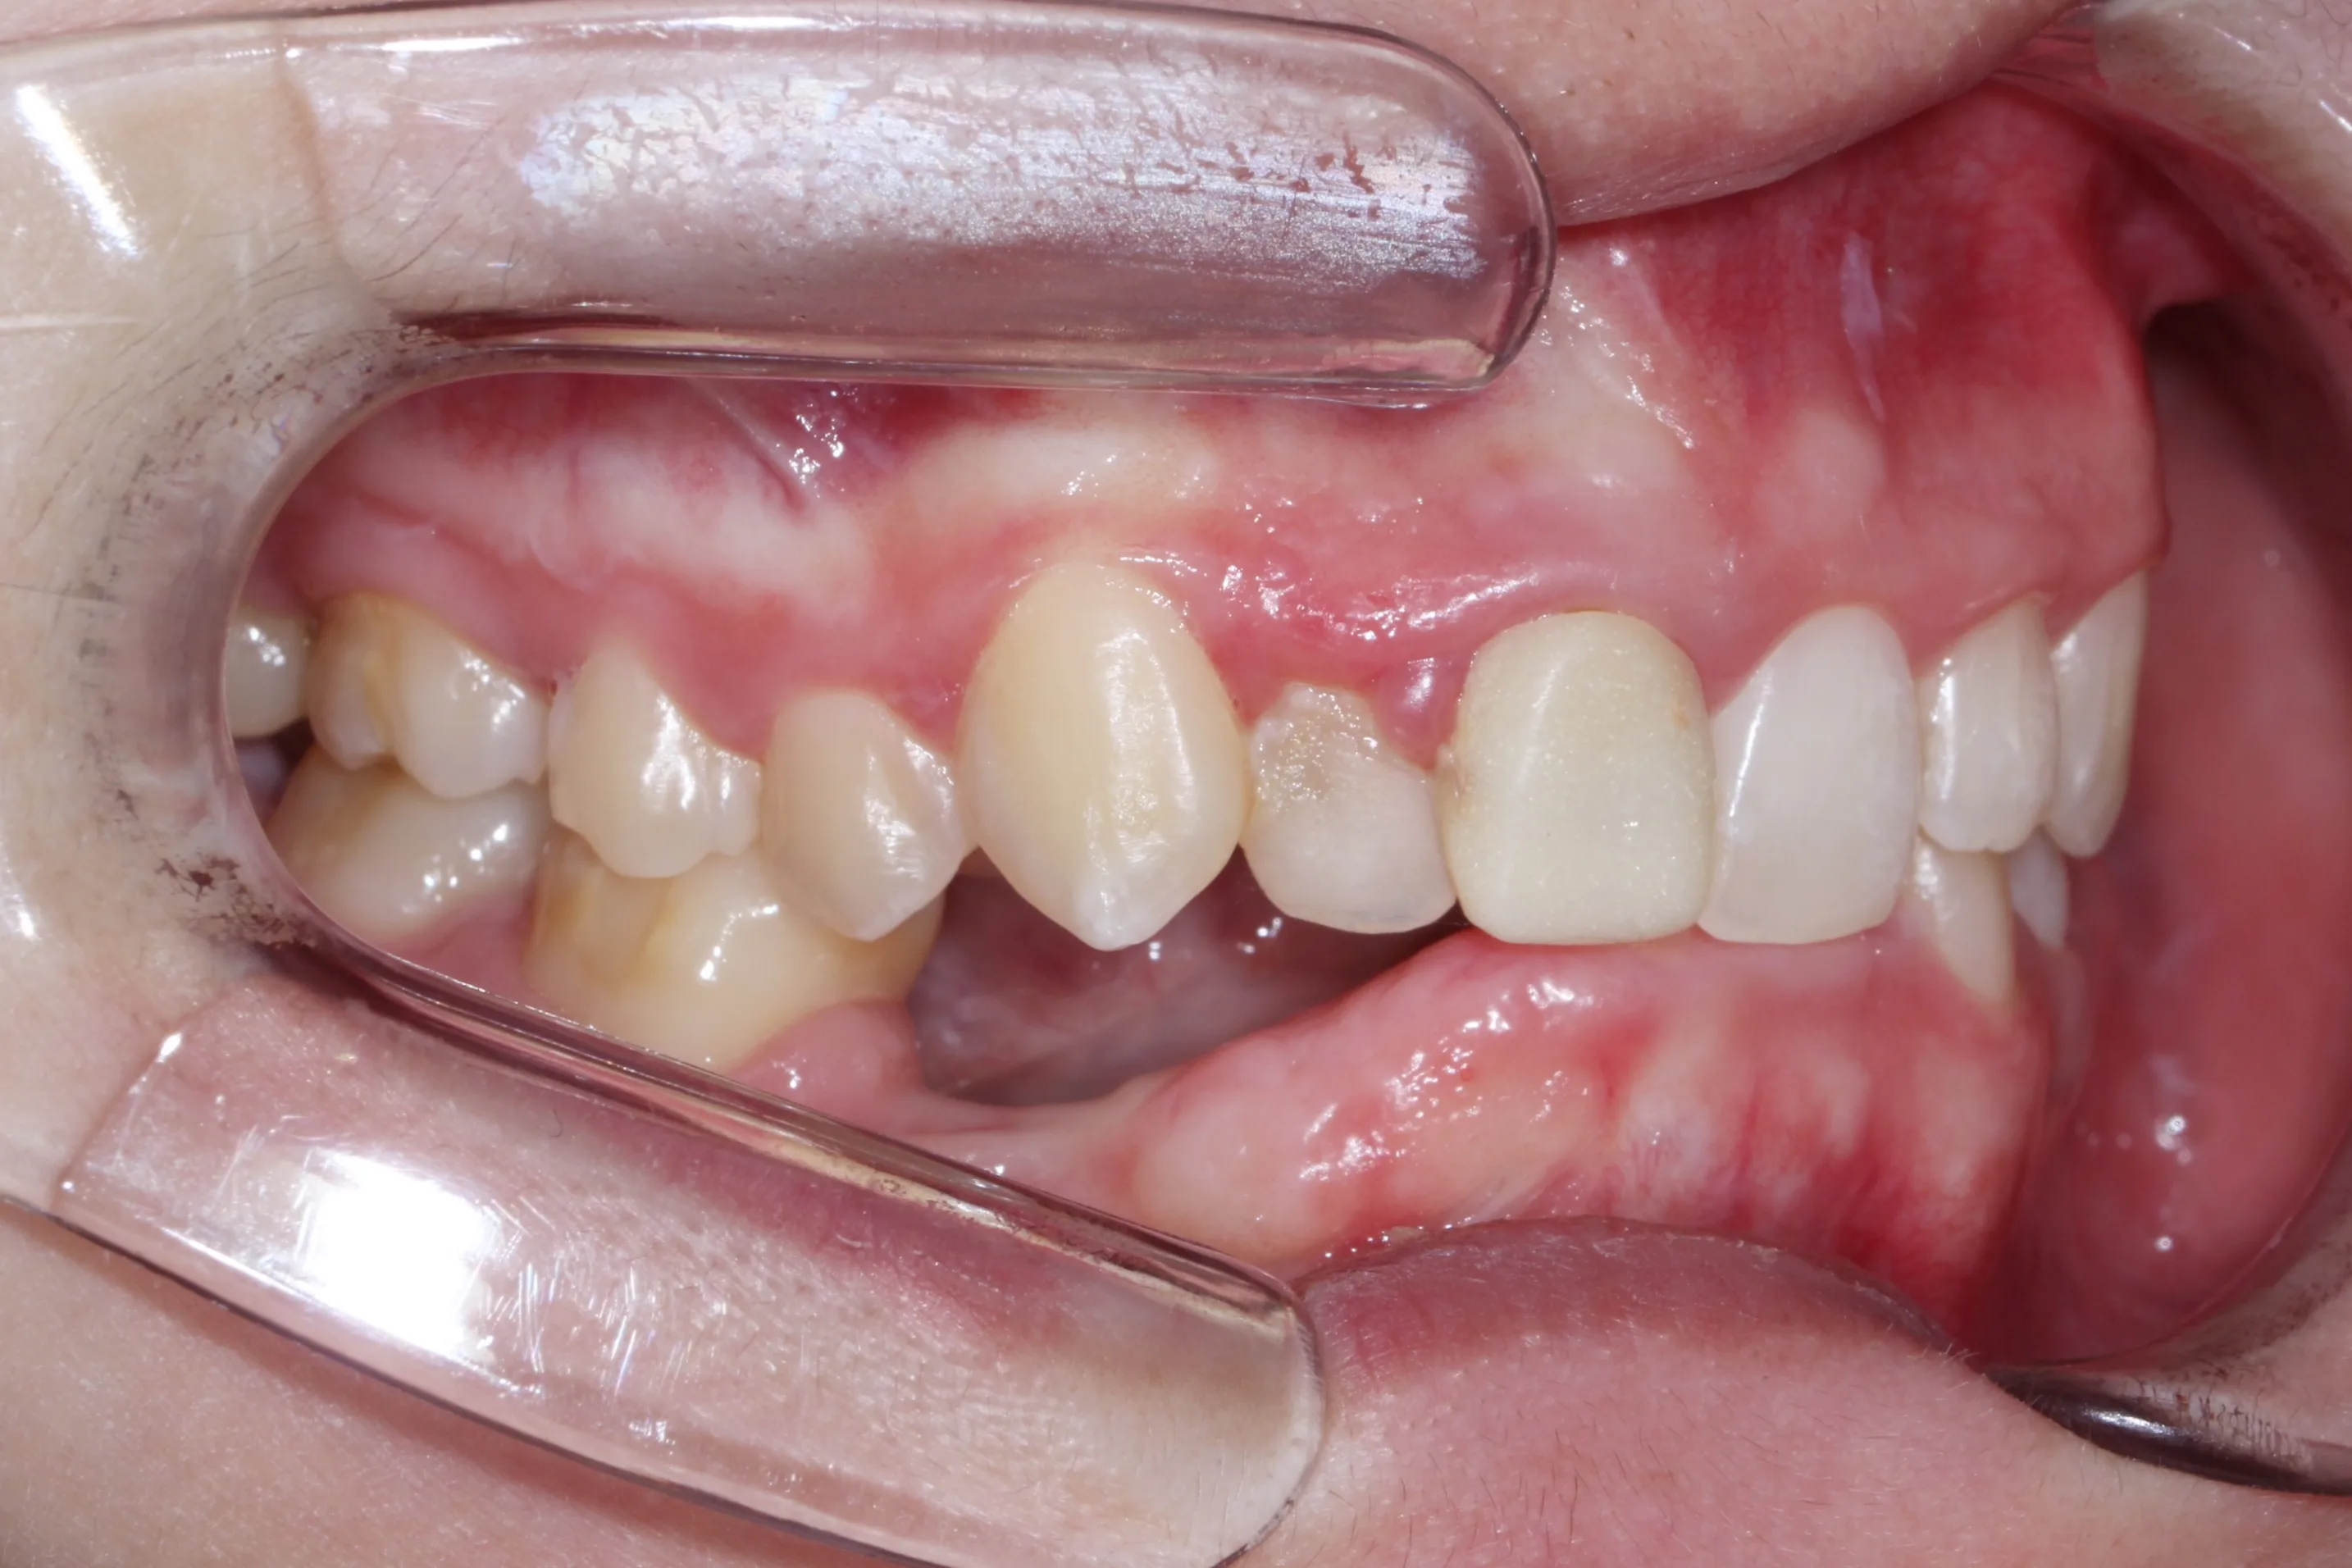

만 21세 환자로, 기존에 사고로 여러 치아를 다치고 상실한 상태로 매우 심한 교합무너짐이 있었습니다.

치료전 (Before)